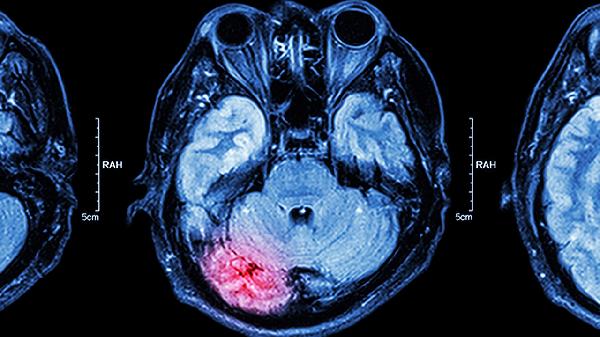

复方脑蛋白水解物片含有多种氨基酸、小分子肽及脑蛋白水解物,能透过血脑屏障直接作用于神经细胞。通过提供神经递质前体物质,调节脑内氨基酸平衡,改善脑细胞能量代谢。临床观察发现该药可减轻脑缺血再灌注损伤,减少自由基生成,保护神经元结构完整性。对于慢性脑供血不足患者,有助于改善头晕、记忆力减退等症状;对于脑卒中恢复期,可促进受损神经通路重塑。

复方脑蛋白水解物片适用于多种中枢神经系统疾病。脑血管意外后遗症期使用可加速运动功能恢复。阿尔茨海默病患者长期服用可能延缓认知功能下降速度。颅脑损伤后应用能减轻脑水肿并缩短昏迷时间。部分周围神经病变如糖尿病周围神经病变也可作为联合用药。少数帕金森病患者使用后震颤症状有所缓解。